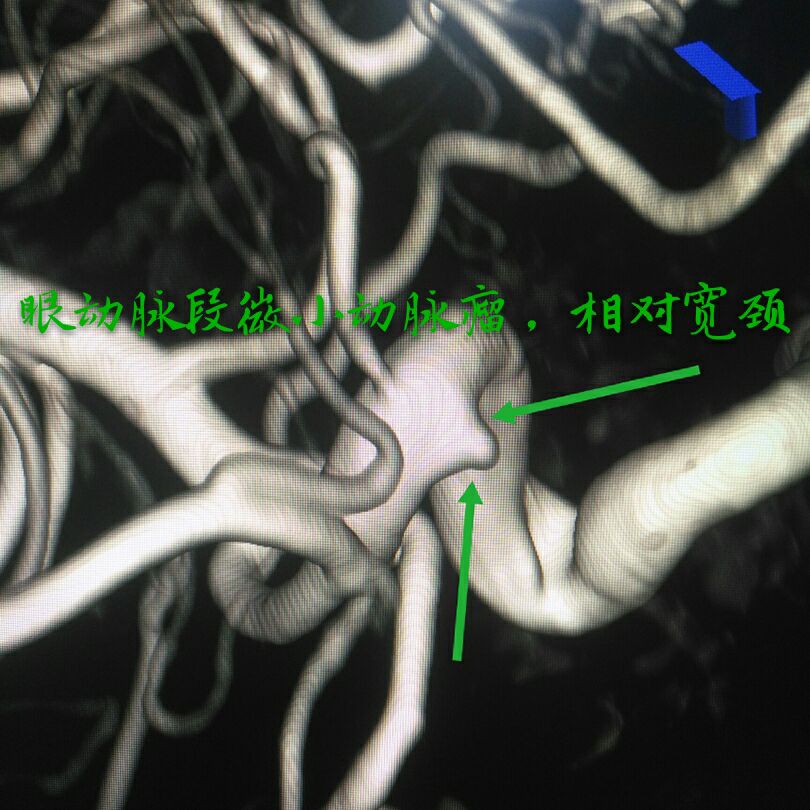

病例七:眼动脉段破裂微小动脉瘤,相对宽颈,呈锥形

支架辅助下用小弹簧圈致密栓塞动脉瘤